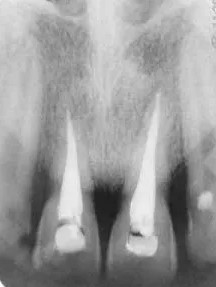

Przykładem zdjęć wewnątrzustnych wykonywanych w pracowni są zdjęcia punktowe zęba, skrzydłowo-zgryzowe i zgryzowe.

Zdjęcie punktowe zęba potrzebne mi było do leczenia stomatologicznego. Dobrze je wykonali, więc stawiam 5.